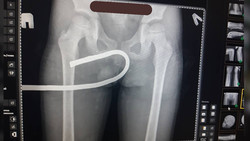

В Оше врачи вытащили из тела 7-летнего мальчика штырь. Фото